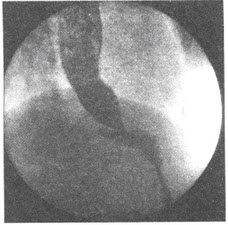

296、单项选择题

患者,男,76岁,食管钡餐造影检查示食管壁张力降低,蠕动减弱,钡剂排空延迟,并在食管中下段见到串珠状充盈缺损影。钡餐检查如下图所示:

下列对该病描述不正确的是()

A.是门静脉高压的重要并发症

B.常见于肝硬化,发生率高达80%~90%

C.早期有明显的症状

D.呕血为主要症状

E.可伴脾大、脾亢或腹水等

点击查看答案